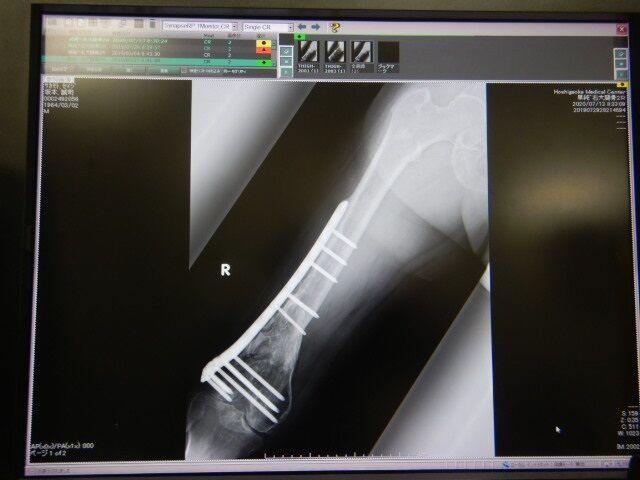

±¦Âǯ¼¡ÅÀ¸¡¤Ø¹Ô¤Ã¤Æ¤¤Þ¤·¤¿¡£±¦²èÁü¤«¤é2018ǯ¡¢2019ǯ¤È¤Ê¤ê

º¸¤Î¥ì¥ó¥È¥²¥ó²èÁü¤¬2020ǯº£Æü¤Î

±¦Â¤Î¥ì¥ó¥È¥²¥ó²èÁü¤Ë¤Ê¤ê¤Þ¤¹¡£